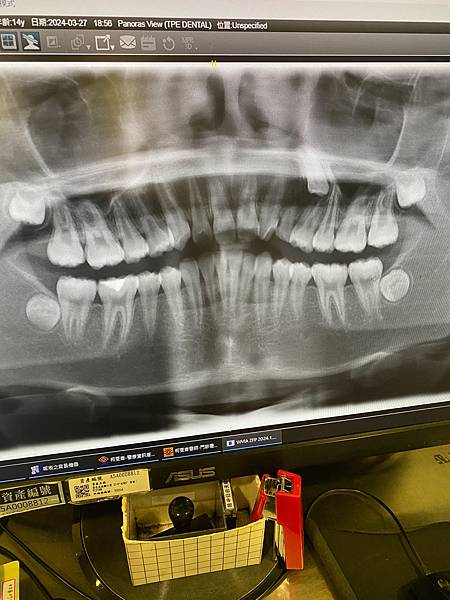

左側上方的成齒已經位移到後面一顆牙的牙齦裡,小乳齒還牢牢就定位,黑黑的部位,顯示牙根已經被吸受,不處理也不行🥹醫生給了兩個方案,自然都各有優缺點,最大的差別是保留那顆還沒長出來的成齒與否!我們決定就先採用保留它的方案一,也只差在一根牙根一萬元,看到總金額16萬時,覺得15萬好像也沒什麼了😅 也沒心理準備今天要矯正,齊齊還跟同學約了要去看電影排球高手!醫生和其他矯正專科牙醫師、牙醫助理都剛好有空,今天就幫他裝上矯正器了,哇喔….有夠神速,也罷,既來之則安之,就這樣吧!裝上矯正器後,變成大鋼牙,醫生也說晚一點會開始牙疼,可以吃普拿疼!原本想就這麼直接回家休息,沒想到齊齊還是要去看電影,好吧,那就去吧😁只能說是個💯隨遇而安的孩子!

因為都國中了,乳齒還沒換完,覺得奇怪,就請牙醫師檢查一下,一檢查發現不對勁,牙醫師建議去大醫院兒童牙科做檢查!

3/27約到北長庚兒童牙科,醫師建議自費3380照全口攝影、也做了全口壓模,等下次回診,會建議我們後續的處理方案!

從三月開始 每個月一次到現在也八次了 目前進展:慢慢把走位到別顆牙齒牙齦上方的成齒拉回到該長出的位置 醫生說下個月應該就可以把下方的乳齒拔掉 讓該正常長出的成齒 從正確位置冒出來 看著照片才能體會一路上真的是個大工程 辛苦小孩 辛苦醫生 一起通力合作努力解決了第一個問題 下個月處理好第二個狀況後 就可以繼續進行下個階段 早診也拖到了一點才看完 出來就近吃了牛肉麵 物價很高大碗半筋半肉已經250了 不過這牛筋燉得非常軟爛 適合牙口不好的我 小孩就喜歡有點牙勁的😅 苦